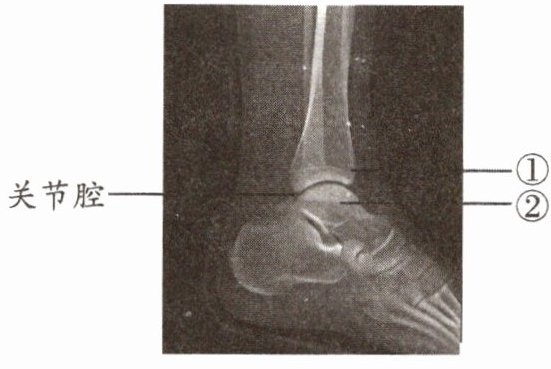

3. 如图为某人左脚的踝关节射线透视图像,①②表示踝关节内的结构。下列说法错误的是(

A.①是关节头,②是关节窝

B.①②表面覆盖着关节软骨

C.关节腔内有滑液,使关节灵活

D.踝关节在运动中起枢纽(支点)作用

A